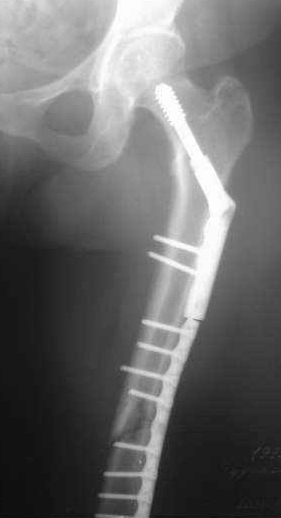

Сегодня мною была осмотрена больная, которой я выполнил накостный остеосинтез около четырех месяцев назад по поводу фрагментарного перелома бедра на уровне средней трети и межвертельной зоны.

Перелом синтезированный DHS сросся, а вот на уровне средней трети - нет. И, похоже, есть нехорошая тенденция к резорбции.

Больную беспокоит умеренный отек голени и стопы. Нагрузку на конечность не разрешаю, ибо недавно у молодого пациента при аналогичном переломе и остеосинтезе произошел перелом пластины на уровне нижней трети бедра...

Обращаясь к Александру Николаевичу, хочется узнать о целесообразности удаления металлоконструкции и интрамедуллярном штифтовании у них в институте у данной больной. Если есть резон, то нужно обговорить финансовую сторону вопроса ...

По поводу моей больной с фрагментарным переломом бедра ...

Больная 47 лет, поступила в отделение после автодорожной травмы от 08 июля сего года с DS: ЗЧМТ, СГМ. Закр. чрезвертельный перелом и перелом с/3 левого бедра со смещением. Ушиб и рваная рана левого коленного сустава. Соп.: Хр. железодефицитная анемия. (Гемоглобин при поступлении 71 г/л). 08 июля - ПХО ран колена.

11 июля остеосинтез бедра DHS + LC DCP.

Я выкладывал на Форум этот случай, где высказывались опасения, что не исключается варусная дислокация межвертельного перелома на фиксаторе из-за малой длины Screw ... вроде пронесло ... перелом сросся. Но маленькая

победа в отдельной битве, все же не принесла победы в целом... Остается неопорная конечность, ограничение движений в коленном суставе 180 - 150 град., отечность голени и стопы, по-видимому, из-за сосудистой недостаточности, гипотрофии

мышц ноги ... При выписке из стационара Hb - 97 г/л (препараты железа, рибофлавины).

По настоящий момент наблюдается амбулаторно. Передвигается с опорой на костыли. Горит желанием встать "на крыло" ... Ждем Вашего решения. Может быть нужны дополнительные снимки?

Возьметесь ли за этот случай? Ну, и самое главное - стоимость лечения ...